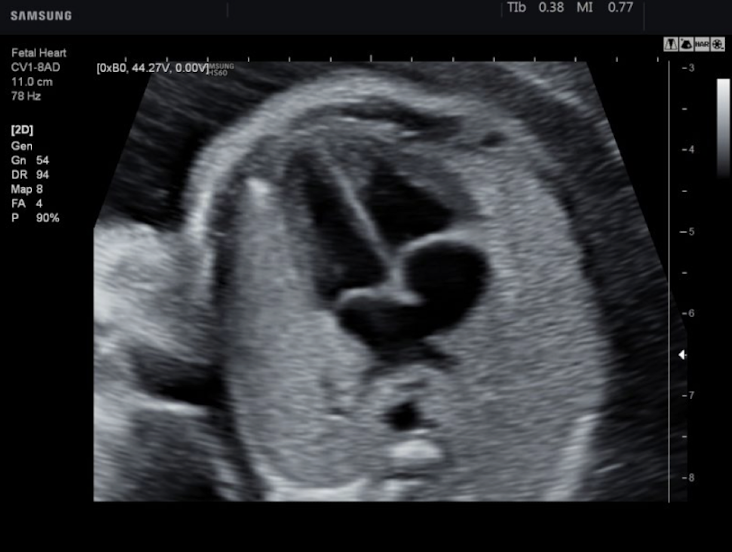

normal or abnormal

normal